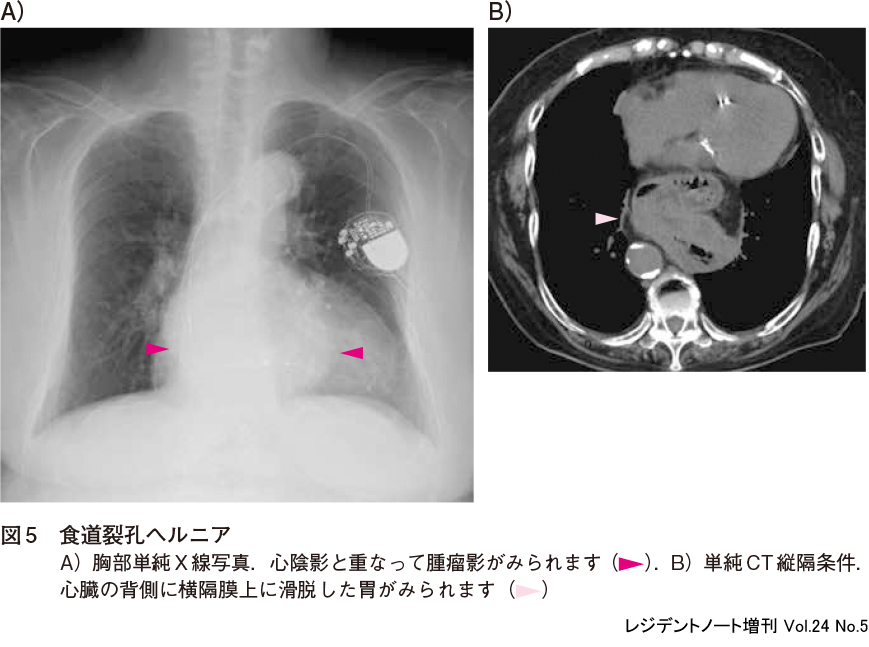

2)食道裂孔ヘルニア

食道裂孔ヘルニアは成人のヘルニアのうち最も頻度が高く,高齢者でしばしば認められます.胸部単純X線写真では心陰影の後方に類円形の腫瘤影として認められます(図5A).縦隔腫瘍や大動脈瘤との鑑別が問題ですが,内部に空気を含み,時に液面を形成することがあることに注意すれば診断できることが多いです.また,左上腹部に胃泡がないことにも注意するとよいでしょう.